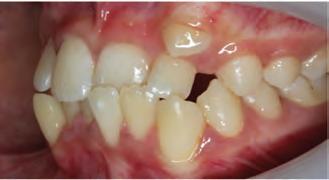

A 31-year-old woman presented with cosmetic concerns regarding her smile and requested a conservative enhancement. After clinical and radiographic analysis, digital 35mm photographs were taken and reviewed by the restorative clinician, technician, and surgeon (Fig 1). A digital impression was taken of the maxillary and mandibular arches using an intraoral scanner (Trios 3, 3Shape; Fig 2), and a smile design was developed with NemoSmile Design 3D software (Nemotec; Fig 3a). This allows for a facially driven smile frame to be created using reference lines of facial and smile proportions and natural teeth shapes and textures from the digital library (Fig 3b).

After developing the simulated mock-up, a 3D-printed resin model was created using CAD software (Fig 4a), and a clear PVS matrix (Exaclear, GC America) was fabricated to replicate the printed diagnostic wax-up using a nonperforated tray (Fig

Fig 1 Preoperative clinical views of a 31-year-old woman presenting with diastemas and limited tooth visibility. (top) Portrait. (center row) Intraoral views. (bottom row) Smile.

4b). This matrix was used to create an intraoral motivational mock-up with bis-acryl composite (Luxatemp Ultra, DMG). This additive mock-up provides the interdisciplinary team with an intraoral translation for evaluation (Fig 5). Upon evaluation of the digital smile frame and the clinical translation, it was determined that multiple esthetic and restorative requirements were necessary for an optimal biologic framework, and the interdisciplinary team determined the best sequence for these procedures. The patient was presented with the interdisciplinary treatment possibilities that included restoring the maxillary anterior teeth and premolars with a minimally

invasive preparationless procedure or with less conservative veneer preparations. The restorative materials discussed included injectable resin composites and ceramic (ie, feldspathic, pressable, machinable). For an optimal biologic framework and health, it was determined that connective tissue grafting would be necessary for treatment of the recessiontype defects on the maxillary left central and lateral incisors, canine, and premolars. The patient opted for the conservative preparationless composite veneers using the injectable resin technique followed by a connective tissue surgical procedure using the tunneling technique.